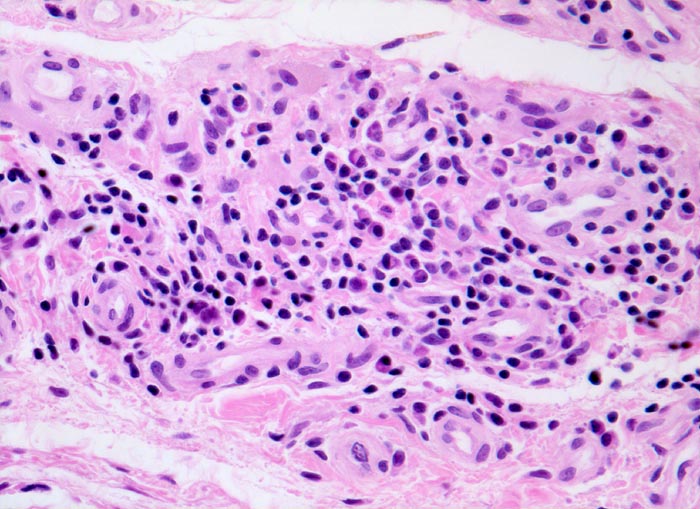

Typische histologische Veränderungen sind eine synoviale Zottenhyperplasie, Verbreiterung der Deckzellschicht unter Einschluss mehrkerniger Riesenzellen, Fibrinexsudate und synoviale Ulzerationen, Infiltrate von Lymphozyten teils in Form von Lymphfollikeln, Plasmazellen, neutrophilen Granulozyten, Makrophagen und Siderophagen, sowie Einschlüsse von Knorpel- und Knochenfragmenten (Detritussynovialitis). Die histologischen Befunde der Synovialis korrelieren oft nicht mit den klinischen Angaben. Trotz fortgeschrittener Gelenkdestruktion mit ausgeprägter klinischer Symptomatik können Synovialektomiepräparate nur sehr geringe pathologische Veränderungen zeigen. Oft ist auch nicht mehr zu eruieren, welche Läsionen Folge der Grundkrankheit und welche Folge diverser intraartikulärer Therapien oder begleitender Superinfektionen sind.

• Stark proliferierte mehrreihige synoviale Deckzellschicht.

• Herdförmig Fibrinauflagerungen durchsetzt von neutrophilen Granulozyten.

• Hyperzelluläres Stroma mit lymphoplasmazellulärem Entzündungsinfiltrat mit Ausbildung von Lymphfollikeln.